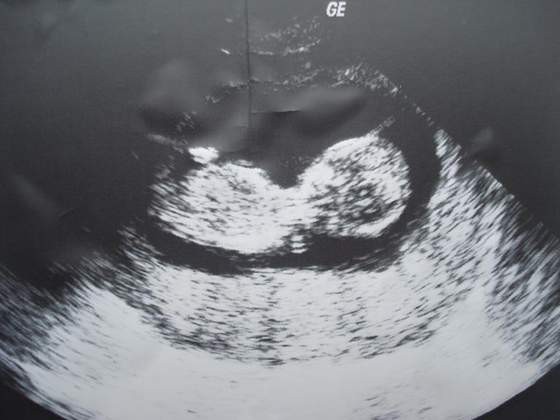

sama słodycz:-) uwielbiam takie zdjęcia oglądać,to jest niesamowite po prostu